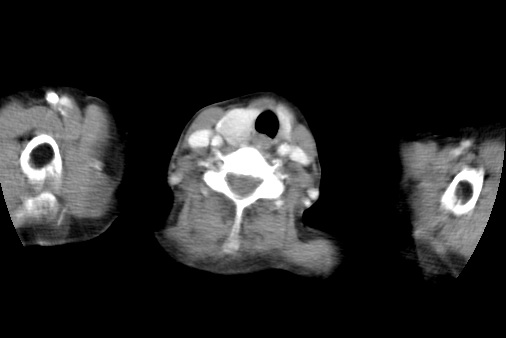

标题: CT23982:女67岁,胸部扫描时发现,甲状腺瘤? [打印本页]

标题: CT23982:女67岁,胸部扫描时发现,甲状腺瘤?

右侧甲状腺腺瘤!支持!不排除甲状腺癌可能!建议手术切除!

右侧甲状腺占位性病变,性质待定(甲状腺腺瘤?);建议:必要时行进一步检查。

右侧甲状腺占位性病变,性质待定(甲状腺腺瘤?);

右侧甲状腺占位性病变,性质待定(甲状腺腺瘤?);建议穿刺活检。

右侧甲状腺占位性病变,甲状腺腺瘤可能,建议穿刺活检。